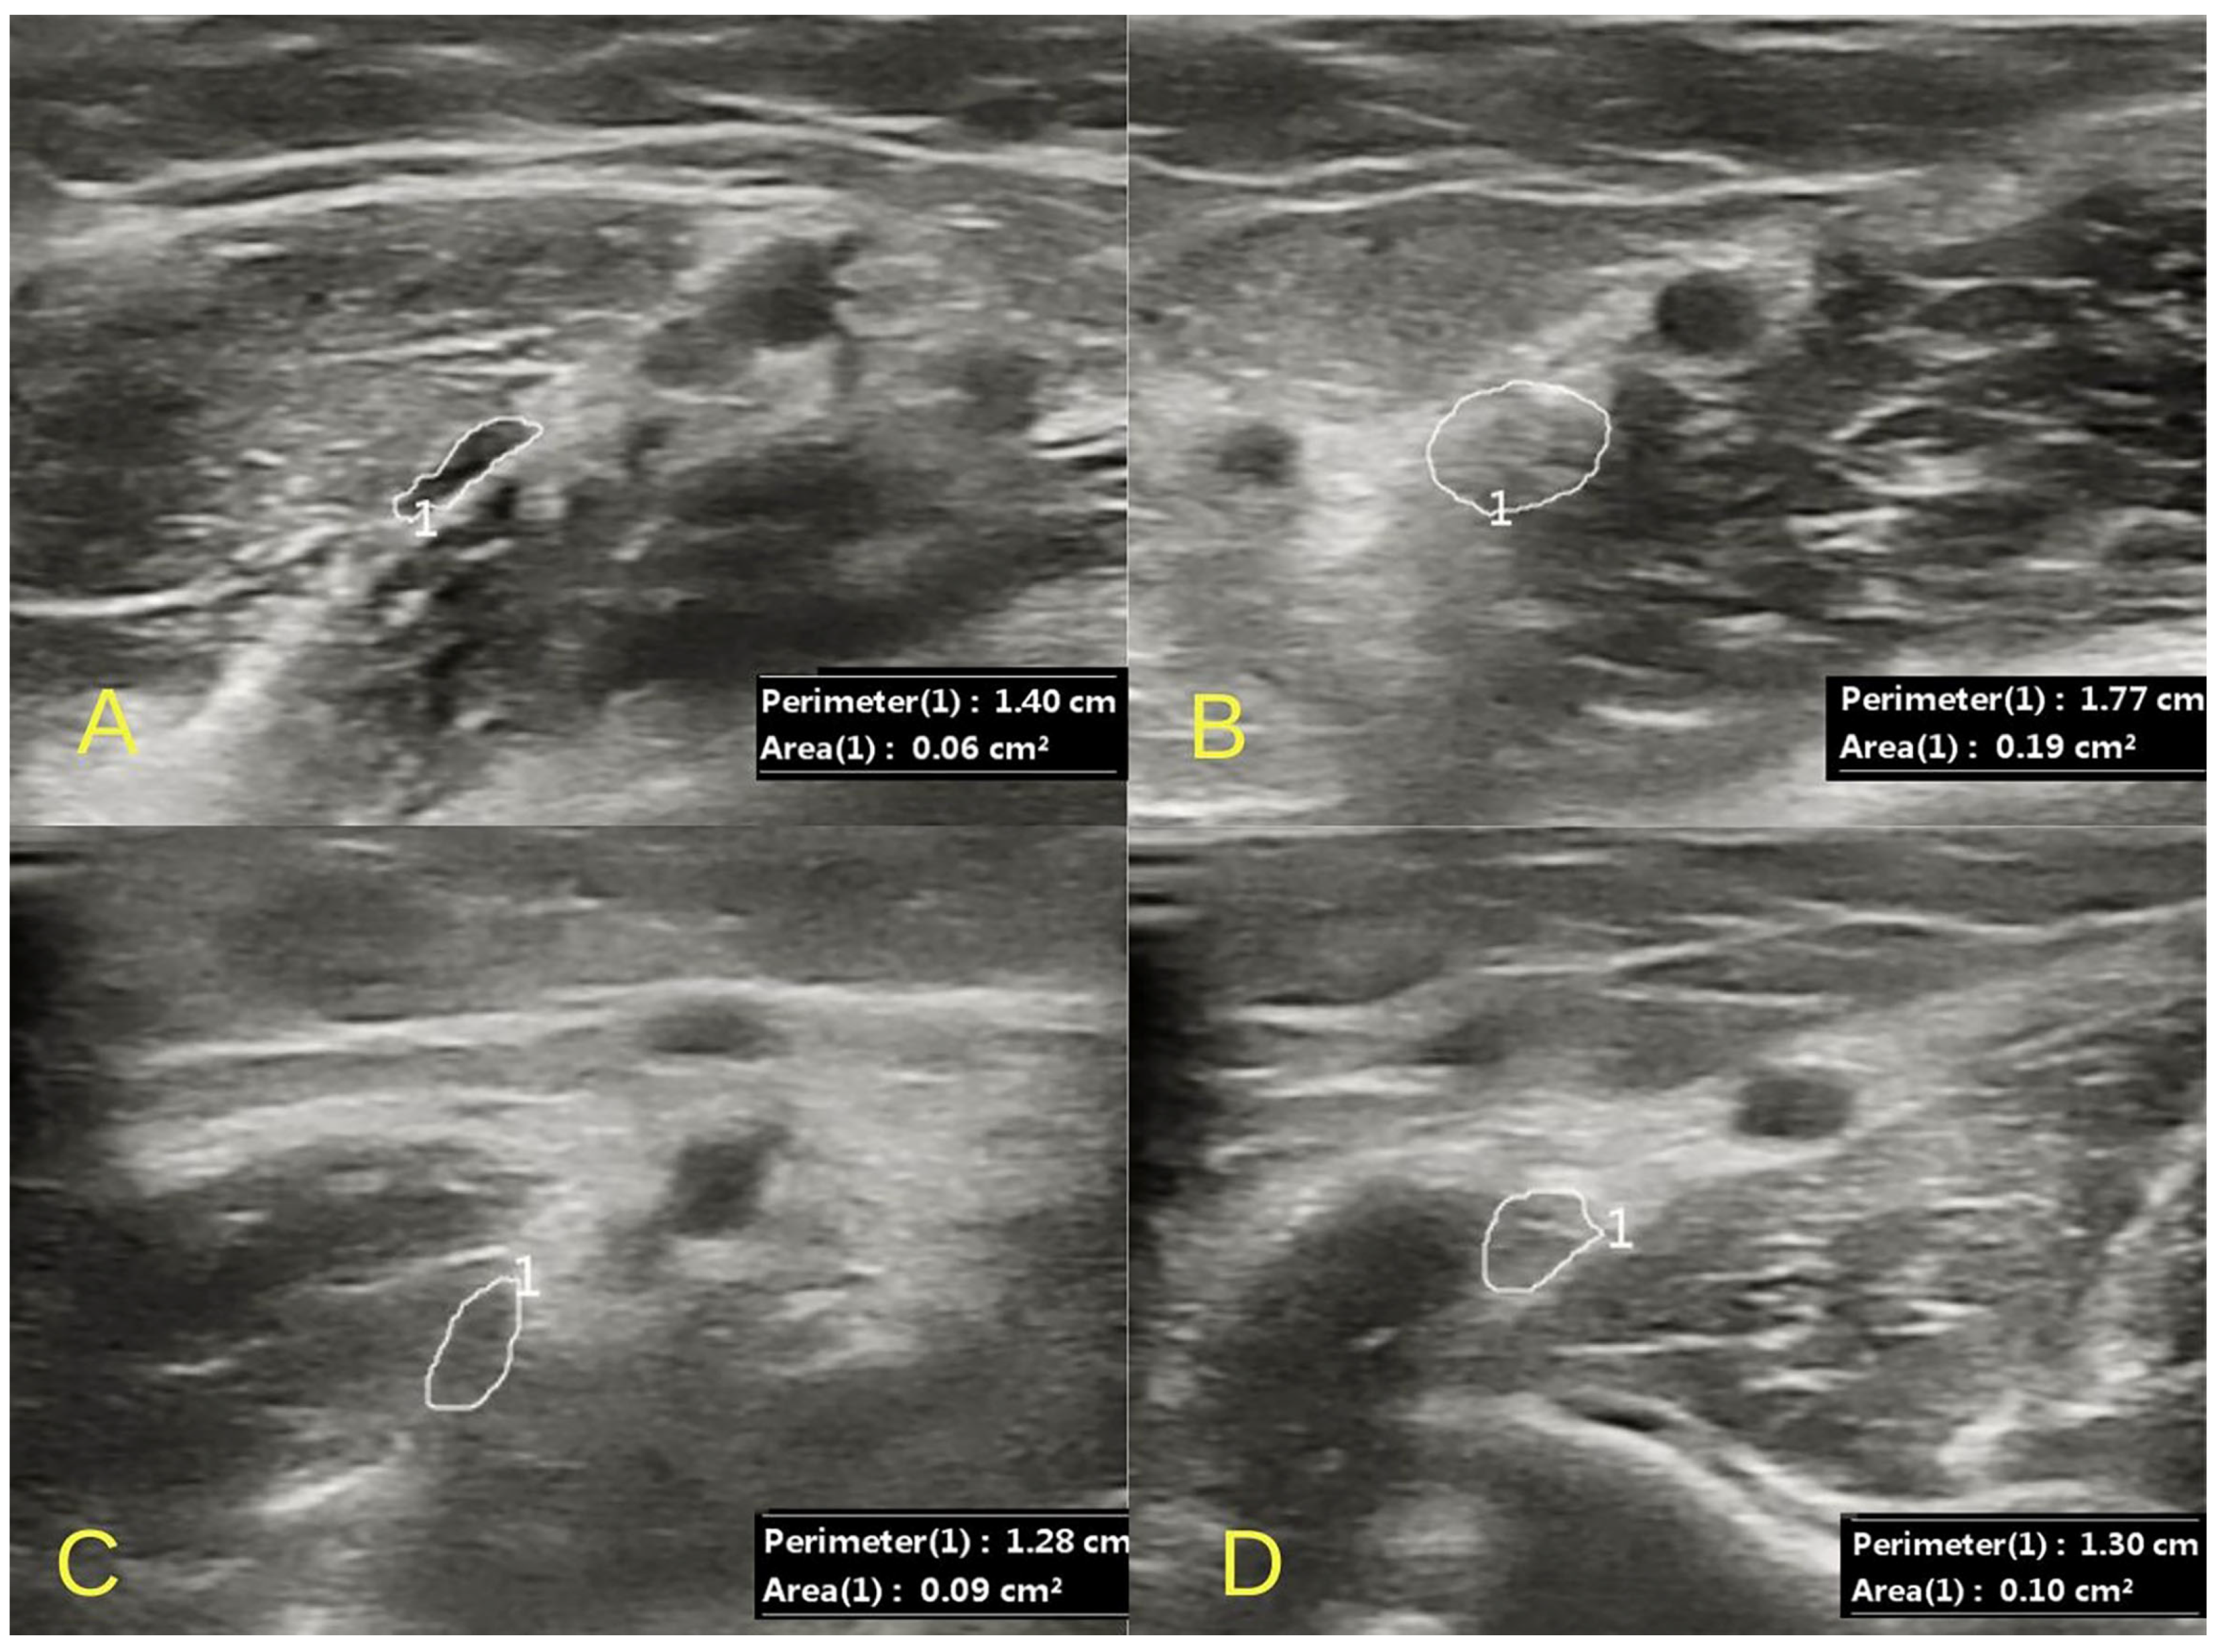

2.1. Clinical Examination and Initial Findings